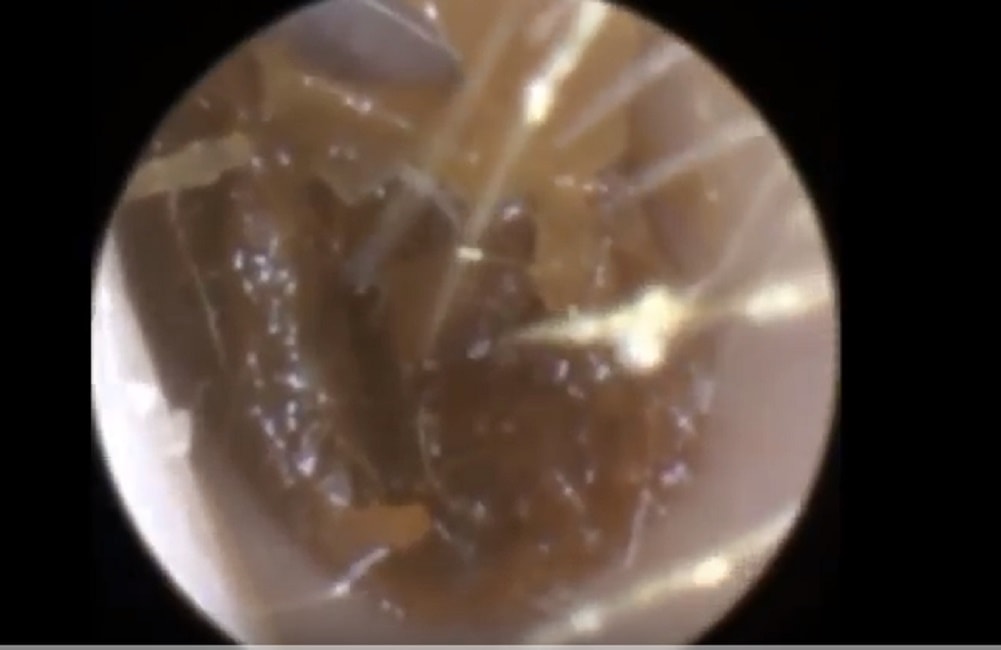

Tappo di cerume rimosso dall'orecchio del paziente

La procedura di pulizia è stata eseguita tramite un endoscopio in una tecnica sviluppata da un medico di nome Neel Raithatha. Il medico spiega che “il cerume era asciutto, opaco ed aveva aderito alle pareti del condotto uditivo”.